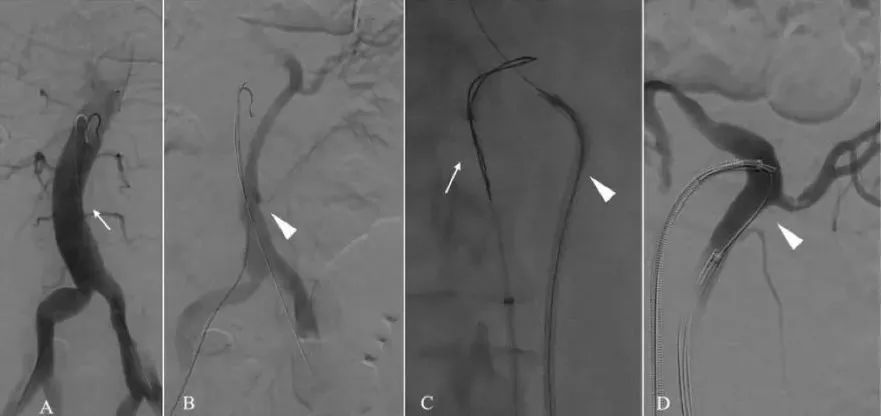

在9例进行内膜片开窗的病例中,有8例从真腔开始向假腔进行开窗,因为假腔较大。在1个病例中,由于假腔中留下的空间很少,所以从假腔向真腔进行了手术(图4)

图4

血管造影显示通电导丝从假腔到真腔。(A)DSA显示真腔(TL)(B)DSA显示假腔(FL),左肾动脉由FL供血(C)从假腔(白色三角)穿过真腔(白色箭头)(D)DSA显示通过路径,允许稳定进入FL(白色三角)